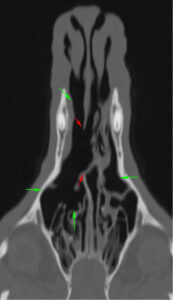

En la TC se apreciaron cambios óseos a nivel de las coanas, compatibles con una malformación congénita asociada o agravada por un posible proceso inflamatorio/infeccioso, que causaba una estenosis marcada de ambas coanas y del aspecto rostral de la nasofaringe (imágenes 1, 2 y 3). Entre los diagnósticos diferenciales de dicha estenosis de tejido blando se incluyeron: un proceso inflamatorio grave o un granuloma infeccioso (principalmente fúngico) sin que se pudiera descartar la presencia de una neoplasia nasofaríngea.

Imágenes 2 y 3. Las flechas rojas indican la lisis completa del tabique nasal en su porción media y la comunicación entre ambas cavidades nasales y las flechas verdes muestran la lisis de cornetes nasales y etmoidales.